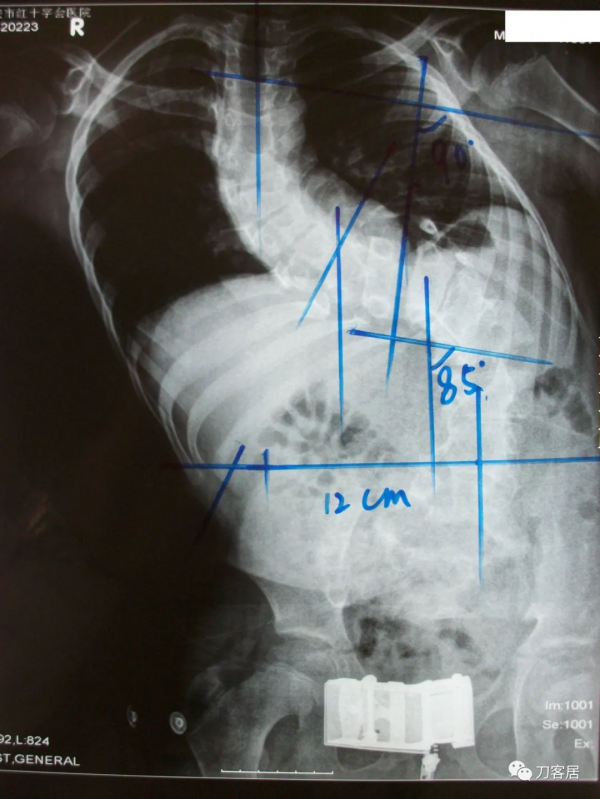

入院診斷:1.先天性脊柱側彎畸形;2.低位脊髓,脊髓栓系。入院後查血常規:WBC 4.30×109/L,RBC 4.83×1012/L,L 41.94%,N 46.54%,HB 134g/L,HCT 41.5%,PLT 295×109/L。尿常規示:PH 5.0,尿比重1.020。糞常規及潛血:正常。凝血四項:PT 12.7s,INR 1.02s,APTT 31.42s,TT 16.20s,FIB 2.27g/L。肝功:AST 32.3u/L,ALT 37.2,TBIL 11.3,IDBIL 7.6,DBIL 3.7,TP 72.3,ALB 45.2,GLO 27.1。腎功電解質:Urea 5.45mmol/L,Cr 51.6umol/L,UA 120.2umol/L,HCO 324.1mmol/L,K+ 3.95mmol/L,Na+ 137.9mmol/L,CI+ 99.1mmol/L,Ca+ 2.25mmol/L。心電圖:竇性心律,心電圖大致正常。胸部X線片:脊柱側彎,胸廓畸形,心肺膈未見異常。腰椎X線片:脊柱生理曲度消失,腰段脊柱向左側凸起,胸10為上端椎,腰5為下端椎,側凸85°,椎體旋轉II°至III°。胸段脊柱向右側突,以胸2為上端椎,胸10為下端椎,側凸90°,胸腰段輕度後凸畸形,Risser徵0級。胸11-腰1椎體分節不全,胸12及腰1及腰2-骶1附件融合。以腰1椎體為中心腰椎向右側凸出。腰1-2椎間隙增寬。診斷結果:先天性脊柱側彎畸形。MRI檢查:胸椎向右側彎曲,所見多胸椎體楔形變,多胸椎間隙不等寬:諸胸椎間盤未見明顯後凸;腰椎脊髓側彎,脊髓位置較低,約平腰3-4水平與硬囊關係緊密。診斷意見:脊柱側彎畸形,脊髓低位,脊髓栓系。心臟超聲檢查:EF55%,心內結構未見明顯異常,左室收縮功能正常,舒張期順應性好,彩色血流未見明顯異常。肺功能檢查:輕度混合型通氣障礙。VC 72%,FEV1 62%, MVV 46%。雙下肢神經電生理報告:DSEP:右側T8、L4,左側T12,雙側T10皮節-皮節P1波潛伏期延長。左側右側雙側皮節內踝-皮層波潛伏期延長。右側L2、5皮節-皮層P1波波幅較對側降低50%以上。視誘發電位CVEP示:雙眼視神經傳導大致正常。

患者術前